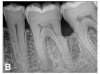

(7.) Progressive improvement in bone quality, quantity, and morphology during each time period, especially in the furcation area of tooth No. 18, which shows a noticeable narrowing of the width of the bony defects, slight apical resorption of the distal root of tooth No. 18, and the encasing of residual cementum on the distal root of No. 19 by new bone formation. Periapical radiographs were taken of teeth Nos. 17, 18, and 19 on June 25, 2016, January 28, 2017, August 23, 2019, and September 4, 2020, respectively, the final of which was taken after almost 5 years post-initial scaling and root planing and alternating supportive periodontal maintenance.

(8.) Progressive improvement in bone quality, quantity, and morphology during each time period, especially in the furcation area of tooth No. 18, which shows a noticeable narrowing of the width of the bony defects, slight apical resorption of the distal root of tooth No. 18, and the encasing of residual cementum on the distal root of No. 19 by new bone formation. Periapical radiographs were taken of teeth Nos. 17, 18, and 19 on June 25, 2016, January 28, 2017, August 23, 2019, and September 4, 2020, respectively, the final of which was taken after almost 5 years post-initial scaling and root planing and alternating supportive periodontal maintenance.

Figure 8

(9.) Progressive improvement in bone quality, quantity, and morphology during each time period, especially in the furcation area of tooth No. 18, which shows a noticeable narrowing of the width of the bony defects, slight apical resorption of the distal root of tooth No. 18, and the encasing of residual cementum on the distal root of No. 19 by new bone formation. Periapical radiographs were taken of teeth Nos. 17, 18, and 19 on June 25, 2016, January 28, 2017, August 23, 2019, and September 4, 2020, respectively, the final of which was taken after almost 5 years post-initial scaling and root planing and alternating supportive periodontal maintenance.

Figure 9

(10.) Progressive improvement in bone quality, quantity, and morphology during each time period, especially in the furcation area of tooth No. 18, which shows a noticeable narrowing of the width of the bony defects, slight apical resorption of the distal root of tooth No. 18, and the encasing of residual cementum on the distal root of No. 19 by new bone formation. Periapical radiographs were taken of teeth Nos. 17, 18, and 19 on June 25, 2016, January 28, 2017, August 23, 2019, and September 4, 2020, respectively, the final of which was taken after almost 5 years post-initial scaling and root planing and alternating supportive periodontal maintenance.

Figure 10

The patient's periodontal disease improved with initial nonsurgical periodontal therapy that involved scaling and root planing. This initial treatment was followed by only SPT every 3 months. Despite treatment, residual deep periodontal probing depths remained, so a decision was made to maximize improvements with nonsurgical therapy and to reassess as needed to determine whether surgical intervention was appropriate. After almost 5 years of SPT and good patient compliance with plaque control and supportive care, the periodontium was stable. Because of the resulting bone formation and improvements in clinical attachment levels (Figure 7 through Figure 13), it was determined that periodontal surgical intervention was not necessary.

In the case report presented, treatment with nonsurgical therapy for 5 years effectively halted destruction and led to bone regeneration and improved clinical attachment levels. Although the primary etiology of periodontal disease is well documented, secondary etiologic and contributing factors are numerous.16 After initial therapy in the current case, there was radiographic evidence of a hypercementosis-like lesion on the distal root of tooth No. 19 (Figure 7 through Figure 10). Hypercementosis is a nidus for plaque accumulation leading to disease progression; however, the presence of this lesion did not explain the disease severity observed for tooth No. 18. Chronic periodontitis is the most widespread form of periodontal disease, and nonsurgical periodontal therapy is the most common type of therapy.17 Scaling and root planning is the gold standard for periodontal treatment. When performed meticulously, they result in improvement of clinical parameters through changes related to tissue shrinkage, long junctional epithelium, new attachment, and in rare circumstances, regeneration.18 The use of nonsurgical periodontal therapy for treatment of periodontal disease requires that the timing for re-evaluation is customized for each patient. Because individuals heal at different rates, the overall medical condition, nutritional intake, environmental and social risks factors, local factors, and colonization of pathogenic bacteria of patients should be considered.7,8 Some patients cannot afford, or choose not to pursue, surgical periodontal therapy. For these patients, clinicians should delay surgical decisions until periodontal risk factors are addressed and nonsurgical efforts are exhausted.